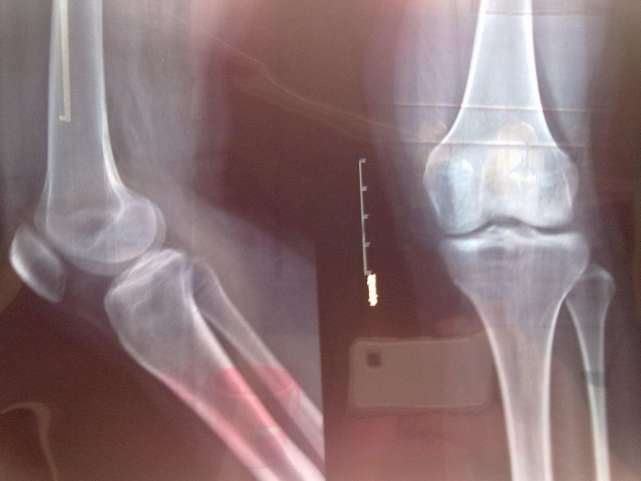

大家都知道骨骺线是骨骼发育的重要标志,对于一个人来说,腿部的骨骺线如果完全闭合,那么他就失去了自然长高的可能性,他们的身高也就不会再发生变化。

每个人的骨骺线闭合时间不确定,如果一些年轻女性怀孕的时候骨骺线还没有完全闭合,那么她们在怀孕期间,因为休息充足、营养比较多,所以她们非常有可能出现“生娃窜一窜”的现象,身高也会变得更理想。